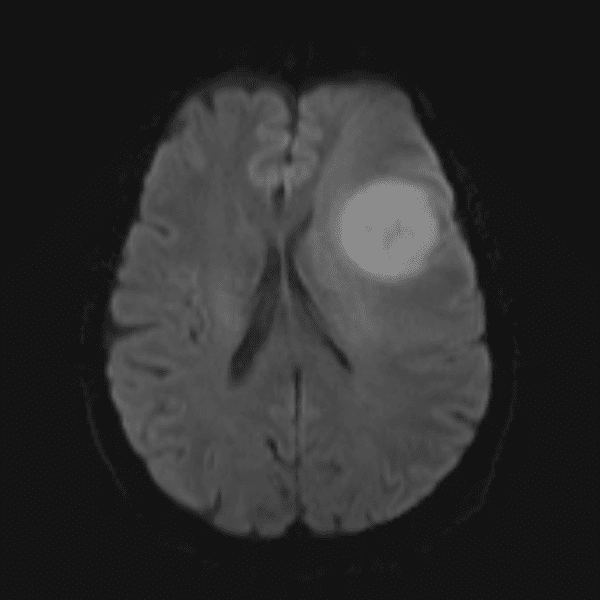

Classic Cases